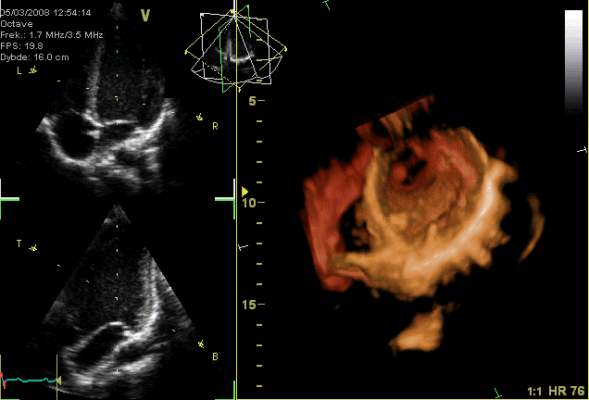

1.3. Hệ thống Van tim

Các van tim đảm bảo dòng máu di chuyển một chiều, hoạt động thụ động dựa trên chênh lệch áp suất.

- Van Nhĩ – Thất (AV): Gồm van ba lá (phải) và van hai lá (trái).

- Các lá van được neo vào cơ nhú thông qua hệ thống dây chằng.

- Cơ chế: Khi thất co, áp lực thất tăng đẩy van đóng lại. Đồng thời, cơ nhú co rút căng dây chằng để ngăn lá van bị sa ngược vào nhĩ. Đứt dây chằng hoặc rối loạn chức năng cơ nhú (do thiếu máu cục bộ) sẽ gây hở van cấp tính.

- Van Bán nguyệt (SL): Gồm van động mạch phổi và van động mạch chủ. Cấu tạo gồm 3 lá van hình tổ chim, không có dây chằng. Hoạt động đóng mở hoàn toàn do áp lực dòng máu. Đóng lại tạo tiếng T2.